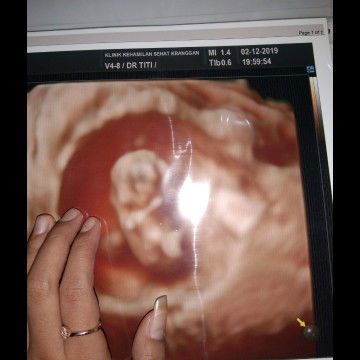

#Sharing_dong_Bund Bun mau tanya di sini ada gak ya yang ngalamin hamil 33minggu sakit dibagian atas mis v bagian tulangnya , sama kali pindah posisi tidur juga sakit+bangun TDR juga sakit .. saat jalan pun juga sama kira2 itu kenapa yaa .. normal atau tidak yaaa